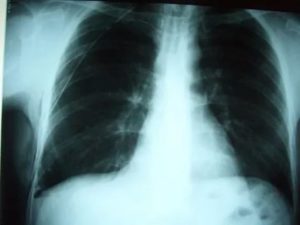

Основным признаком спаечного процесса на легком является наличие тени, которая появилась на снимке. Стоит учесть тот факт, что она никак не изменяет свою форму при вдохе и выдохе. Наряду с этим легочное поле будет менее прозрачным, а диафрагма и грудная клетка могут быть несколько деформированы. Зачастую спайки наблюдаются внизу легкого.

Для обнаружения легочных заболеваний в первую очередь используется флюорография. Эту процедуру необходимо проводить ежегодно, в основном она направлена на выявление ранней стадии туберкулеза. Однако опытный рентгенолог может выявить на снимке образовавшиеся плевральные спайки, которые выглядят тенями. Причем форма их не меняется в зависимости от вдоха и выдоха.

При необходимости дополнительно назначается рентген. Как правило, спайки располагаются в нижней части легкого. При этом будет более темная картинка, а также может быть частичная деформация грудной клетки и диафрагмы.

Основной атрибут, указывающий на спайку справа, является тень, видная на Rg-снимке. При этом затемнение не изменяется при вдохе и выдохе пациента. Одновременно снижается прозрачность легочной поверхности.

В тяжелых случаях наблюдается деформирование грудной клетки и диафрагмальной области. При таком состоянии диафрагма ограничивает свою подвижность. Чаще всего такие спайки расположены в нижних отделах легкого.

Распознать спайку по снимкам можно, если на нем легкие мутные, а еще при сравнении фотографий на вдохе и на выдохе. Спайка выглядит как тень, положение которой не меняется во время дыхания. Иногда наблюдается изменение формы и ограничение подвижности диафрагмы и грудной клетки.

Чаще всего спайки обнаруживают в нижней части легких.